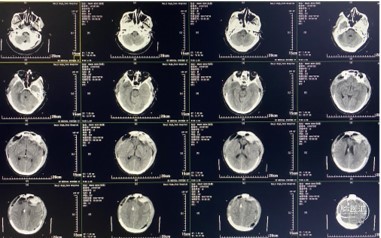

5月26日CT(术后第7天)

CT提示:环池、三脑室、双侧侧脑室显露良好